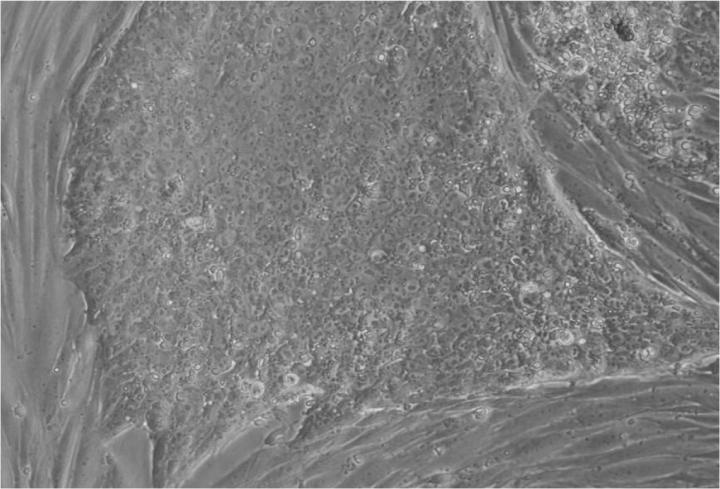

人類胚胎干細(xì)胞 (ESC) 是從囊胚(一種非常早期的人類胚胎)中發(fā)現(xiàn)的少量細(xì)胞產(chǎn)生的。從囊胚中取出的單個細(xì)胞生長成大量細(xì)胞以產(chǎn)生 ESC“系”。

胚胎干細(xì)胞的自我復(fù)制能力允許從干細(xì)胞系中培養(yǎng)出大量細(xì)胞,并與全球?qū)嶒炇夜蚕矶嗄辏瑥亩畲笙薅鹊販p少了從囊胚制造新胚胎干細(xì)胞的需求。

胚胎干細(xì)胞研究的重點是干細(xì)胞系。這些是細(xì)胞群,都攜帶相同的基因,在實驗室中通過許多代細(xì)胞的許多生長和分裂周期生長。一個細(xì)胞系可以為許多研究人員提供大量細(xì)胞。

Jenny Nichols 拍攝的人類囊胚和人類胚胎干細(xì)胞圖像。愛丁堡大學(xué) MRC 再生醫(yī)學(xué)中心向 SCNT 和多莉羊注射細(xì)胞核。